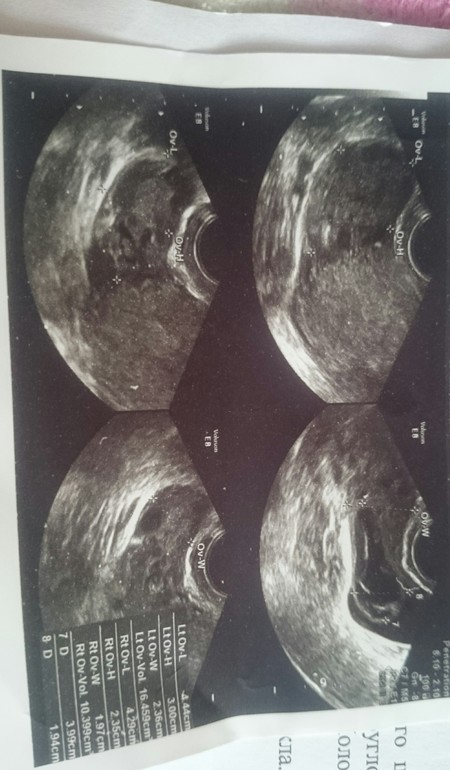

Цикл у меня 28-34. Недавно впервые в жизни на 18 д.ц. пошла кровь. Сходила на узи. Вот результат. Узист толком как всегда ничего не объяснил. Сказал - воспаление у тебя. Но недавно сдавала мазок,всё было идеально(( Девочки, всё совсем у меня плохо? Смогу ли я вообще когда-нибудь забеременеть? Разъясните,пожалуйста. Очень буду ждать ваших ответов. Сижу плачу..

Эндометрит нужно лечить,конечно. Сдайте посев с чувствительностью к антибиотикам. Хронически эндометрит лечится сначала антибиотиками, потом физиотерапией и витаминотерапией. Про кисту не поняла, она у вас первый раз на узи или давно? Может это фолликулярная киста, она сама уйдет через 1-3 цикла. Жёлтое тело есть, значит О была. Вылечите воспаление и сможете забеременеть, конечно. Не надо плакать, все будет хорошо)

Врач описывает признаки хронического воспаления. В данный момент едва ли можно говорить об обострении, так как протекает оно с лихорадкой и изменением анализа крови, который Вам стоит сдать. По поводу яичников - не совсем поняла, почему не вынесли в заключение жидкостное образование, описанное в протоколе. Кровь , вероятнее всего, была в момент овуляции. Это вариант нормы, если эпизод был однократный и не длительный. Сейчас вам лучше заняться решением вопроса о дообследовании эндометрия.